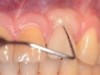

The entry of inflammatory cell infiltrate into the connective tissue (Figure 1 and Figure 2) differentiates peri-implantitis from peri-implant mucositis.1 Unlike a natural tooth—where periodontal fibers, transepithelial fibers, and gingival fibers absorb this exudate—none of these fibers are present around an implant (Figure 3). This allows the inflammatory cell exudate to directly enter the bone, resulting in bone loss and concomitant soft-tissue loss (Figure 4).1

Fig 1. In the pathogenesis of peri-implantitis, inflammatory cell infiltrate enters the connective tissue.

Figure 1